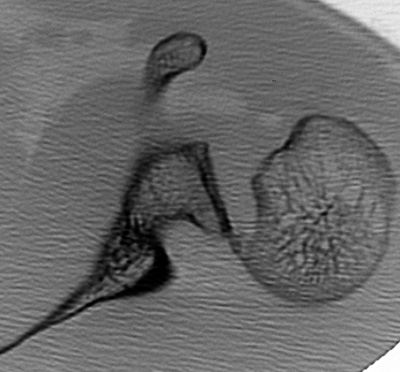

Figura 4: A) T.A.C. simple: Cuantificación u locación del defecto óseo en la región antero-medial de la superficie articular humeral. Fragmento libre en cavidad. B)3-D: Valoración y cuantificación del fragmento osteo-condral y su relación al momento del estudio.

Figura 7: Aspecto macroscópico del fragmento libre Osteo-condral con una delgada capa de hueso esponjoso subcondral.

Figura 8: Preparación del FLO mediante perforaciones.

Figura 9: Colocación de dos anclas metálicas de 2,8 mm (Fastak®, Arthrex®), al lecho, realización de una sutura en puente, previa reducción mediante “pull in”.

La experiencias previas con el manejo de las fracturas osteo-condrales de la rótula secundarias a luxaciones, sirvieron de modelo para evaluar y tratar el F.L.O. hallado. Diversas técnicas son recomendadas, van desde: la extirpación del fragmento, el injerto osteocondral, forage, y/o reposición mediante diversos sistemas de fijación.24,25 En 2008 Bower y cols. describen el concepto de la sutura puente para una fractura osteocondral de cóndilo femoral.2

Los factores considerados para la fijación del fragmento osteo-condral fueron: a) tamaño, b) localización, c) presencia de estrato o capa ósea remanente.26

La fijación de este F.L.O. puede ser un objetivo difícil de lograr, especialmente, cuando el remante óseo es una fina capa laminar. Los alambres de Kirschner o tornillos, resultan a veces ineficaces en estas situaciones debido a la debilidad biomecánica de la fijación. La fijación en puente mediante una sutura de tipo colchonero con anclajes en el defecto óseo, presenta una ventaja para la fijación de fragmentos osteocondrales con poco hueso sub-condral, ya que proporciona una compresión a través del lugar de la lesión mediante el mecanismo “pull in” del sistema y logra estabilidad de la fractura, lo que permite el movimiento postoperatorio inmediato, evitando la necesidad de retirar el implante.